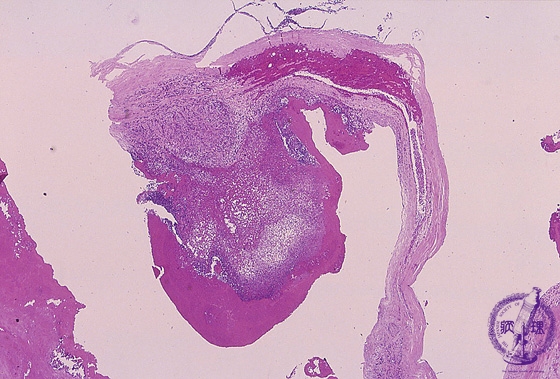

Microscopic image (HE, low power view): Infective endocarditis of the mitral valve. Bacterial colonies which contain infiltrating neutrophils form vegetations with subsequent valvular destruction.